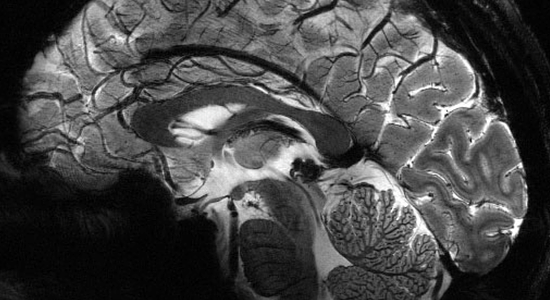

Le cerveau se dévoile

Dans le cadre de la 26ème édition de la fête de la science, SimUSanté® vous invite à découvrir plus en profondeur un organe de notre corps qui évolue sans cesse, notre cerveau.